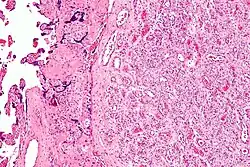

Micrograph of a chorangioma. H&E stain. | |

- Chorangioma